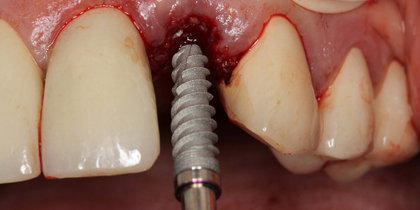

Simplify Implant Surgery — From Single Units To The Full Arch

Glidewell HT Implants are specially designed to perform in even the most demanding clinical cases. View case studies to learn how Glidewell HT Implants are used in the following situations: limited space, immediate provisionalization, edentulous ridges, extraction with immediate placement and single-unit posterior.

• A Glidewell HT is immediately placed into the extraction socket of a maxillary central incisor. thumbnail image

Extraction with Immediate Placement

A Glidewell HT is immediately placed into the extraction socket of a maxillary central incisor.

• A Glidewell HT Implant is immediately placed following the extraction of tooth #19. thumbnail image

A Glidewell HT Implant is immediately placed following the extraction of tooth #19.